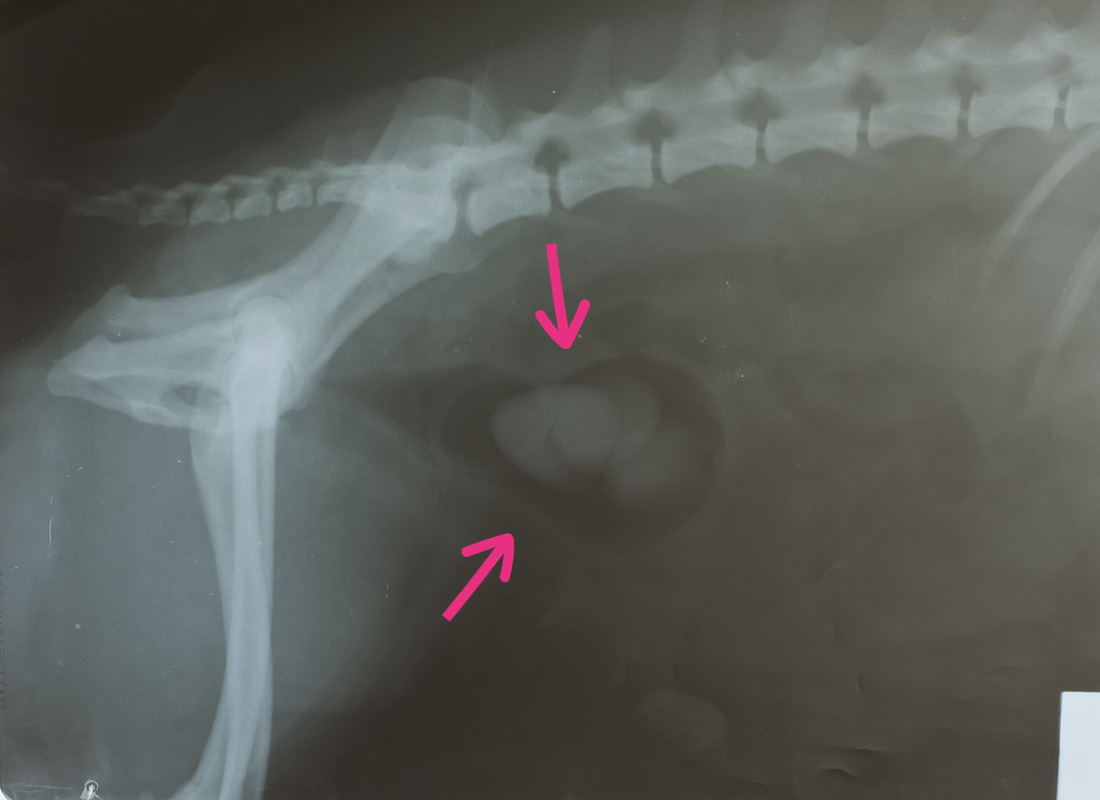

Your vet will ask you some questions about your dog and will feel your dog’s tummy. If they have large bladder stones your vet may be able to feel them, but it’s likely that they will need to carry out further tests, such as X-rays or an ultrasound of the bladder to confirm. A special dye is sometimes injected into the bladder to make the stone appear bright on x-rays.